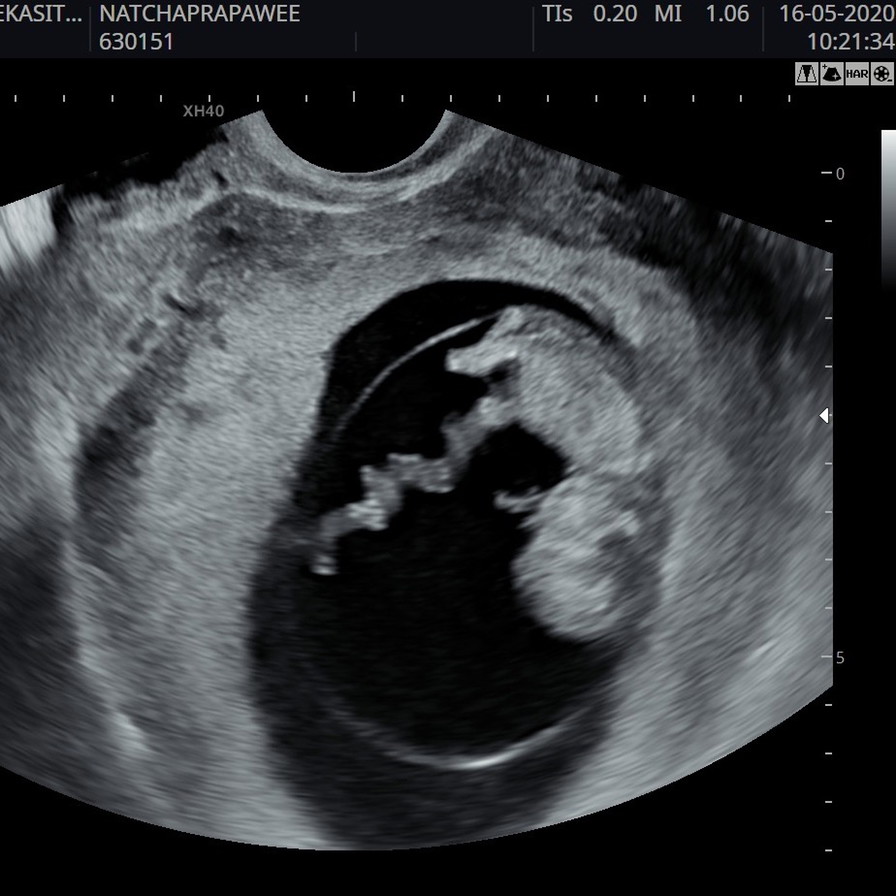

ขอดูใบซาวหน่อยจ้า เเล้วกำหนดคลอดวันที่เท่าไรกันค่ะ

1ธันวาค่ะ ตอนนี้11w6d